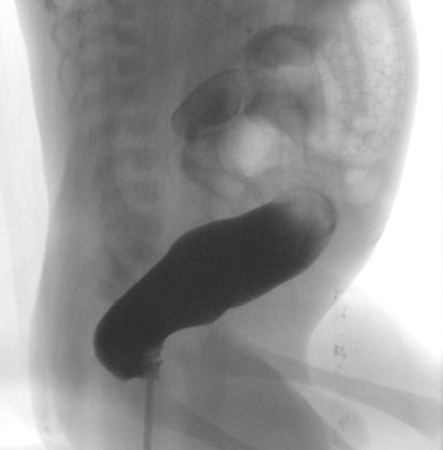

A contrast enema performed with water-soluble contrast material is the most valuable imaging test for Hirschsprung's disease. A contrast enema is recommended if the clinical evaluation is suspicious for Hirschsprung's disease or if there are signs of distal obstruction on x-ray. A rectosigmoid ratio (maximum diameter of the rectum divided by maximum diameter of the sigmoid colon during contrast enema) of <1 is highly suggestive of Hirschsprung's disease. Other suggestive findings include retained contrast at >24 hours, mucosal irregularity, or microcolon.[48] A transition zone may be seen on contrast enema but this may be less obvious in neonates.[49] A transition zone on contrast enema can help with surgical planning, but it should be noted that the radiographic transition zone may not correlate with the histological transition zone.[50] Contrast enema may demonstrate mucosal irregularity in the aganglionic distal colon and may show a transition zone between smaller calibre aganglionic distal colon and dilated proximal ganglionic colon.[Figure caption and citation for the preceding image starts]: Barium enema performed in a newborn with Hirschsprung's disease. Often, classical changes are not obvious in the neonatal periodCorman ML. Colon and rectal surgery. 5th ed. Philadelphia, PA: Lippincott Williams and Wilkins; 2005:555-603; used with permission [Citation ends].

[Figure caption and citation for the preceding image starts]: Contrast enema showing an abnormal rectosigmoid ratio (sigmoid diameter larger than rectal diameter)From the personal collection of Lily Cheng, MD; used with permission [Citation ends].